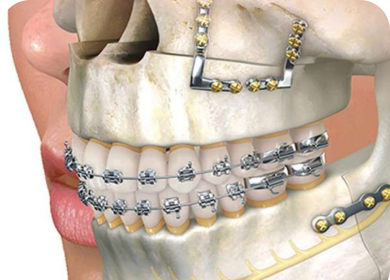

Our oral surgery services address complex dental and jaw-related issues with precision and care. From tooth extractions and impacted wisdom tooth removal to corrective jaw surgery and implant placements, we ensure every procedure is performed with the highest safety standards, minimal discomfort, and optimal healing for our patients.

We offer modern orthodontic solutions, including traditional braces and clear aligners, to straighten teeth, correct bite issues, and enhance facial aesthetics. Our personalized treatment plans ensure optimal results while prioritizing comfort, discretion, and efficiency for patients of all ages.